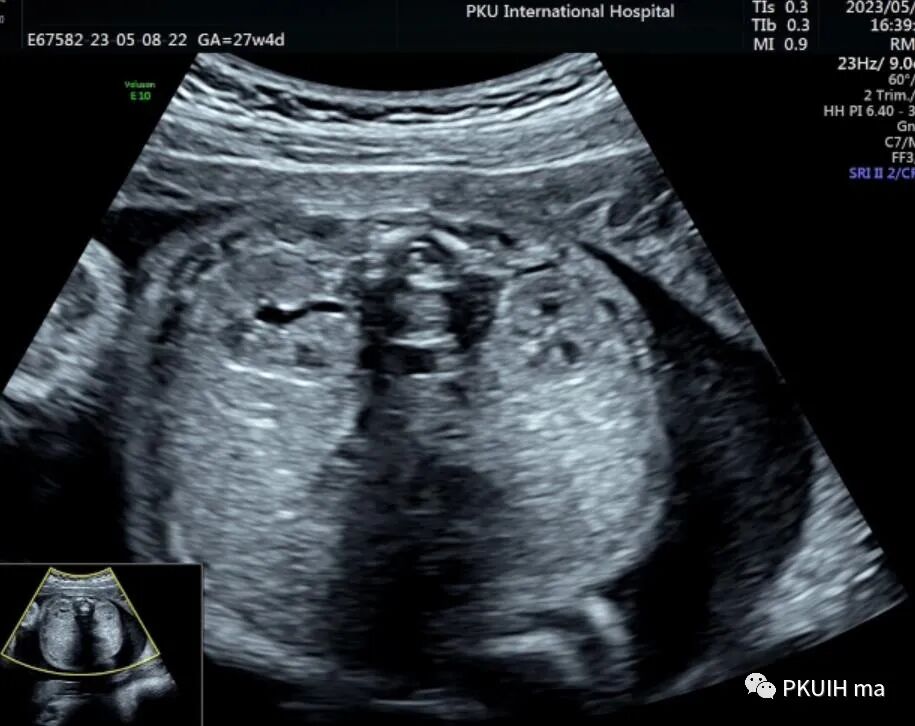

下图分别是23周和27周正常胎儿的肾横断面图像,显示肾门呈水平状,指向内侧,分离的肾盂也呈水平状